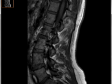

МРТ:

Тело L5 смещено кзади на 4 мм.

В L5-S1 сегменте диффузная протрузия диска кзади, в том числе фораменально до 5мм, с оттеснением неотечной задней продольной связки, с компрессией корешков выходящих на этом уровне, в том числе и за счет сужения невральных каналов, оттеснены корешки, выходящие с обеих сторон под S1. ширина СМК 18мм.

Заключение: МР-картина дегенеративно-дистрофических изменений пояснично-крестцового отдела позвоночника в виде остеохондроза с протрузией диска и нестабильностью в L5-S1 сегменте.

Диагноз из стационара: дискогенная радикулопатия L5 справа, ахиллов рефлекс справа снижен, симптом Ласега справа 30гр.